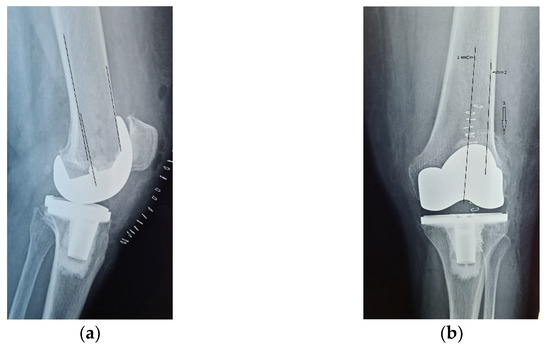

Four years ago, the patient was diagnosed with Ahlback stage IV gonarthrosis and underwent a simultaneous bilateral TKA surgery in another orthopedic clinic. Two NexGen cemented total prostheses were then implanted, with patellar resurfacing performed only on the right side, due to anesthetic complications which required a drastic shortening of the operating time, thus preventing the surgical team from performing resurfacing on the contralateral patella. Although postoperative radiological images showed a slight implantation error in the femoral component on the right side, extensive anterior resection with posterior rotation of the femoral component, the clinical outcome was satisfactory (Figure 1).

Figure 1.

Right knee, initial after surgery radiological image: (a) lateral view, extensive anterior resection, femoral posterior rotation, femoral component axis intersecting diaphyseal axis at a 15.4° angle with (1) marking the femoral diaphyseal axis and (2) marking femoral component rotation axis; (b) coronal view.

On the other hand, on the left side, where patellar resurfacing was not performed, although the radiological images show a satisfactory implantation of the prosthesis with correct alignment of the tibial and femoral components, but with slight subluxation of the patella, the clinical evolution was unsatisfactory (Figure 2). Shortly after operation, 3–4 weeks, the patient experienced discomfort, pain and swelling of the left knee.

Figure 2.

Initial radiological aspect of the left knee, right after surgery: (a) lateral view, femoral component axis parallel with femoral diaphyseal axis; (b) coronal view, slight lateral patellar subluxation (arrow) compared to femoral axis with (1) marking the femoral trochlear axis, (2) the patellar axis, and (3) patella must be centered in the femoral trochlea.